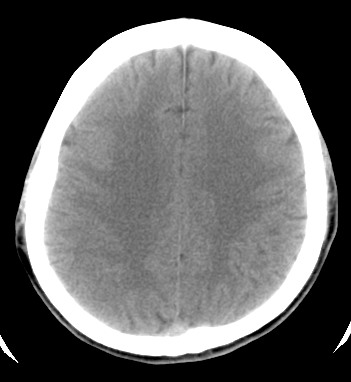

标题: CT17787:头ct,请帮忙看看右顶部有无异常 [打印本页]

男,58岁,偶有头疼

未见明显异常。右顶部低密度影为深入的脑沟。

增宽的脑沟!无异常!

是宽大的脑沟,局部不象有萎缩现象

增宽的脑沟

诊断依据:

低密度影周围脑组织边缘均有一层脑灰质覆盖。

正常啊,是对右顶增宽脑沟有疑问吗